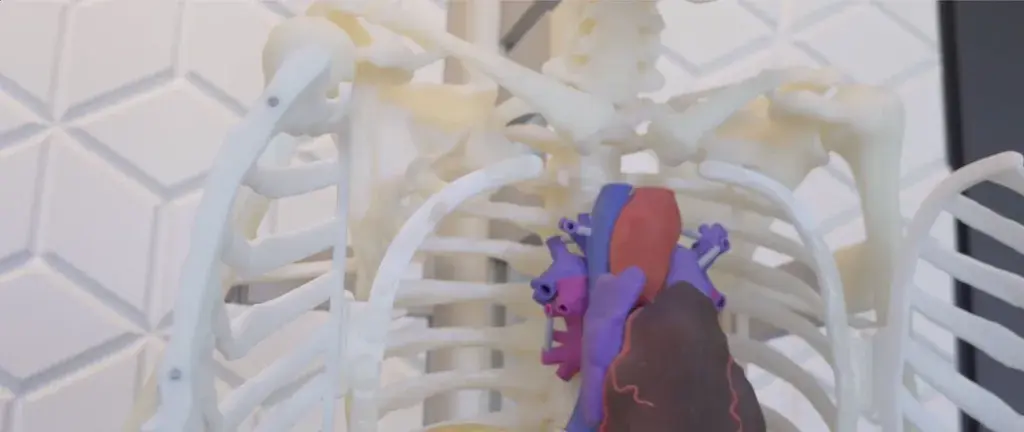

Since each patient's anatomy is different, patient-specific anatomic models provide an opportunity to visualize and plan surgeries prior to entering the operating room. In addition, you can use anatomic models to educate patients and their families on an upcoming procedure.

Validated Printers and Proven Materials

Strong, durable models in medical-grade nylon materials*